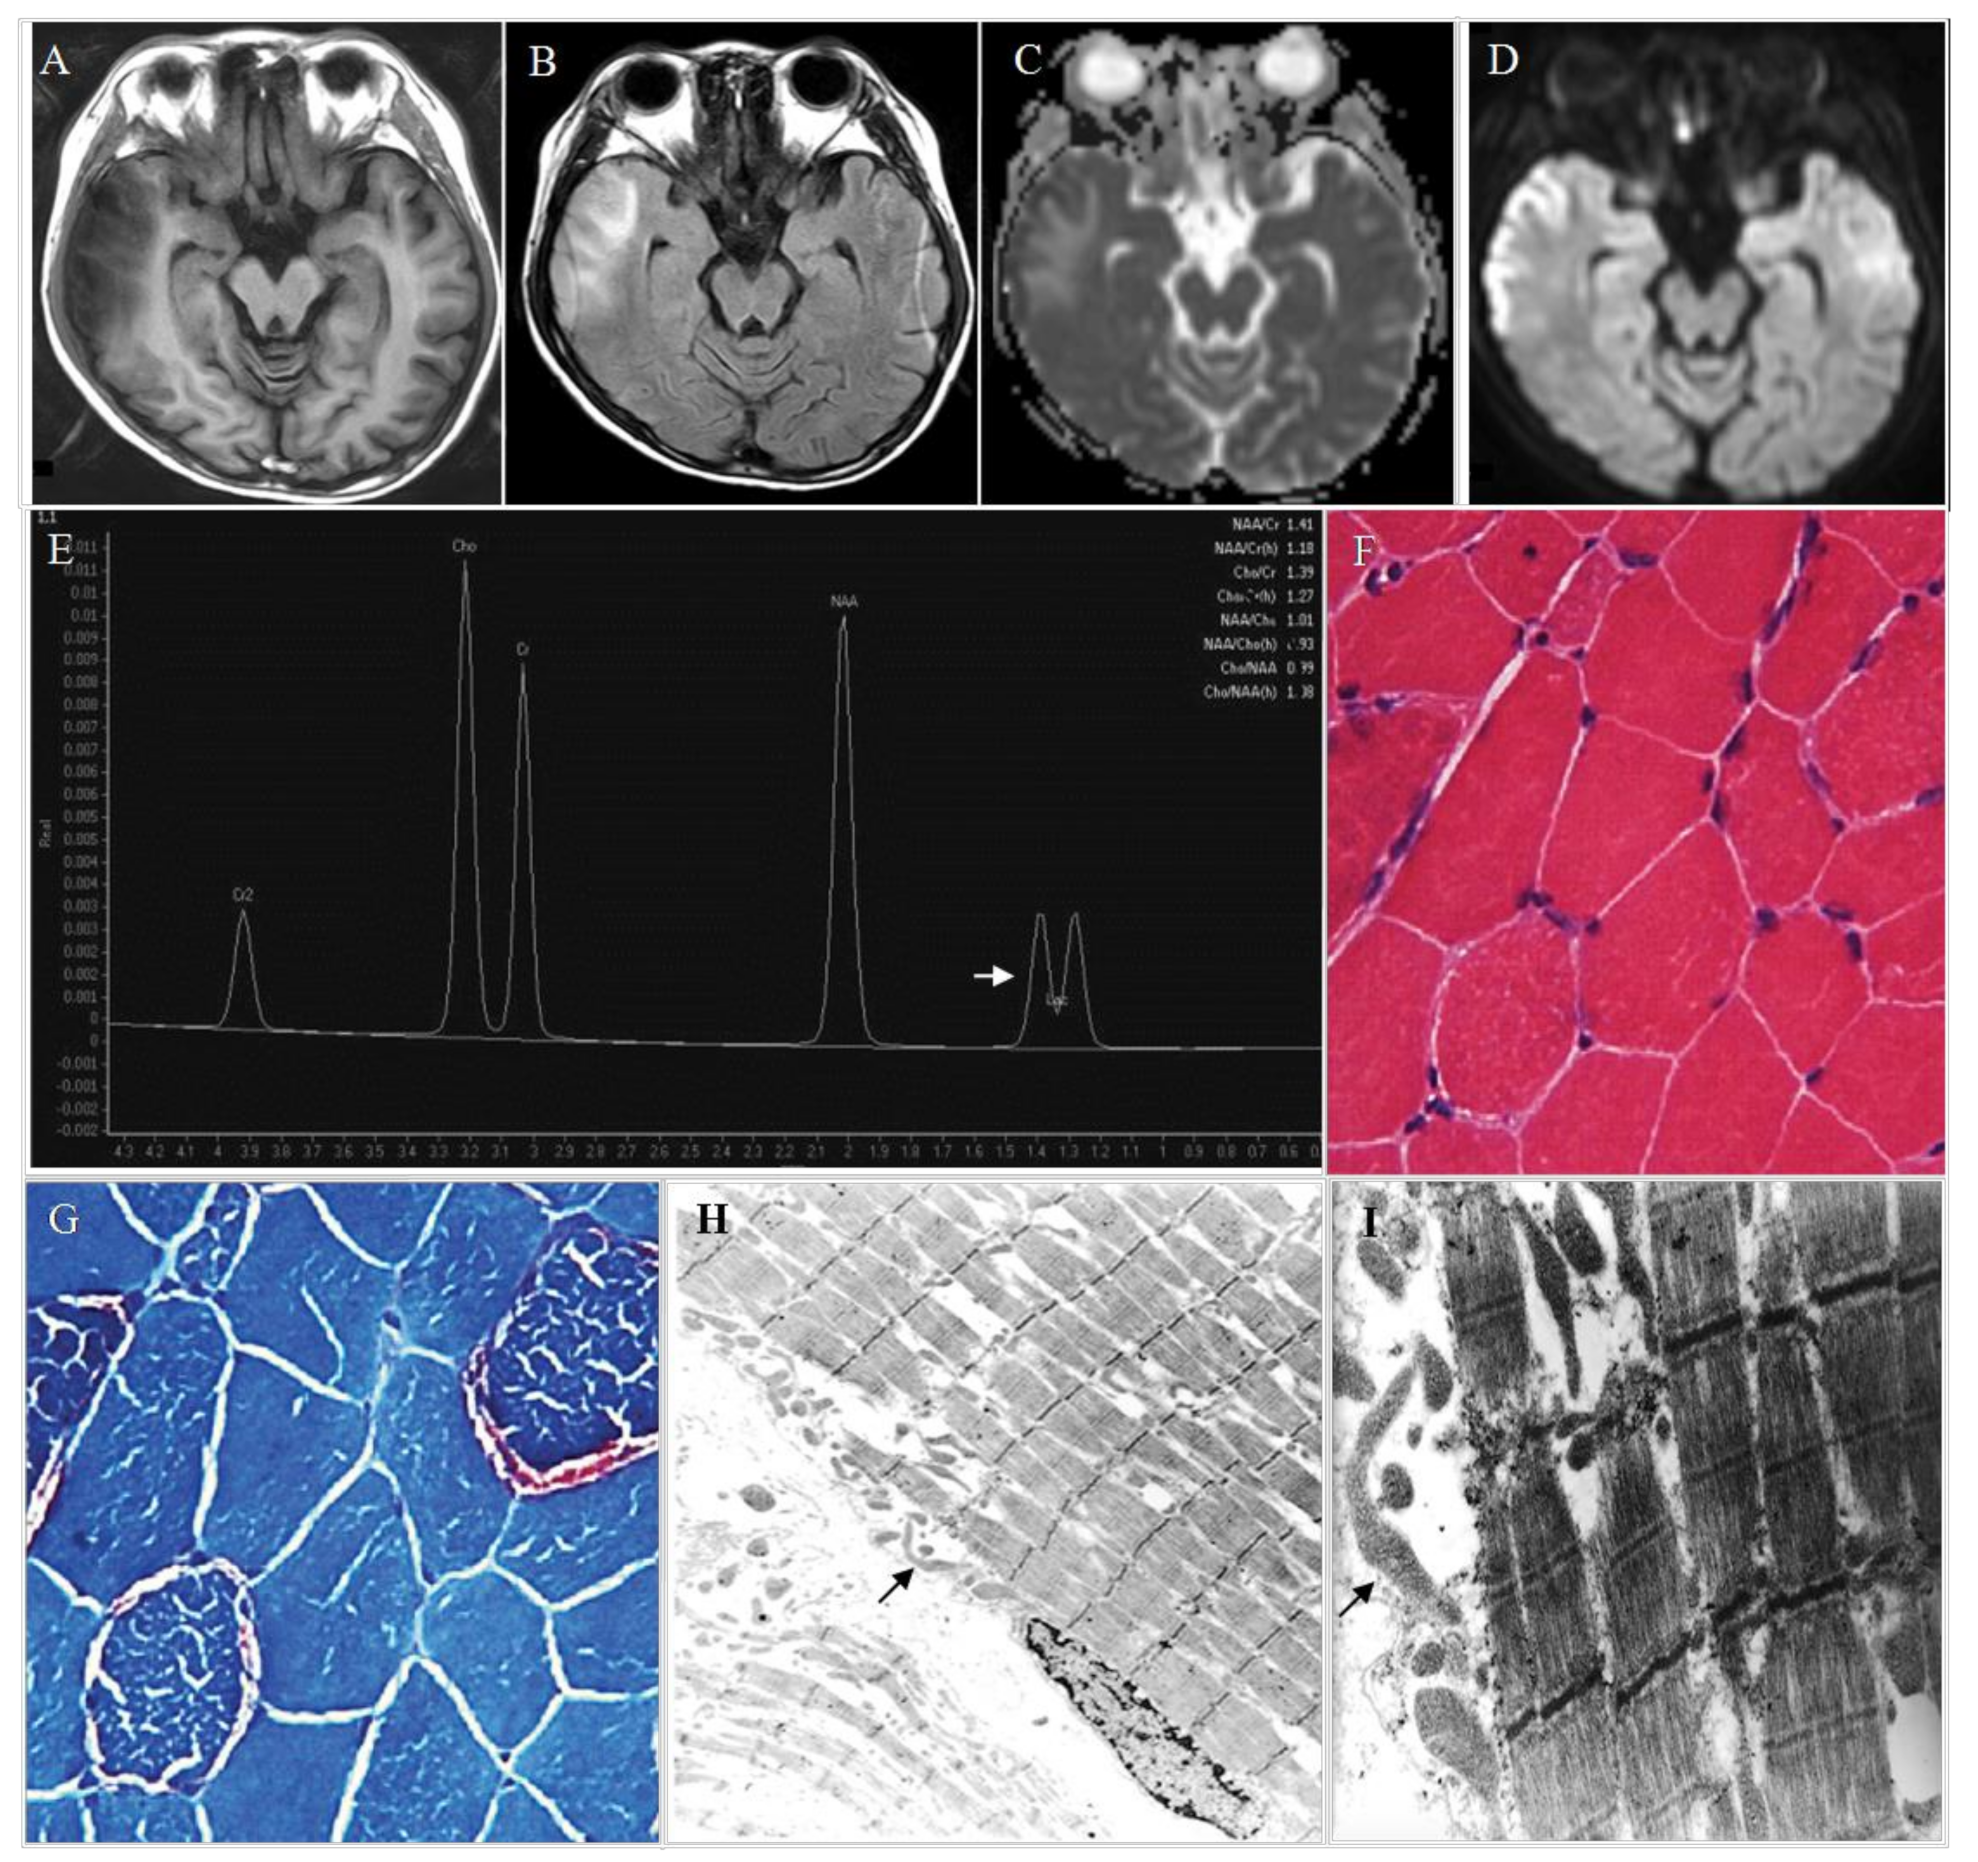

4. Diagnosis